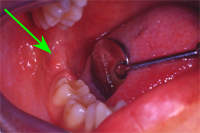

Abb. 1 zeigt das klinische Bild vor der Aufklappung. Der Pfeil markiert die Stelle, wo der Weisheitszahn unter der Schleimhaut im Knochen liegt. Vor der Operation musste ein CT zur transversalen Lagebeurteilung des sensiblen, wichtigen Lippennerves zur Wurzelspitze des Zahnes angefertigt werden. In der CT-Schichtaufnahme von Abb. 2 wird ersichtlich, dass der Weisheitszahn sehr tief unten liegt.